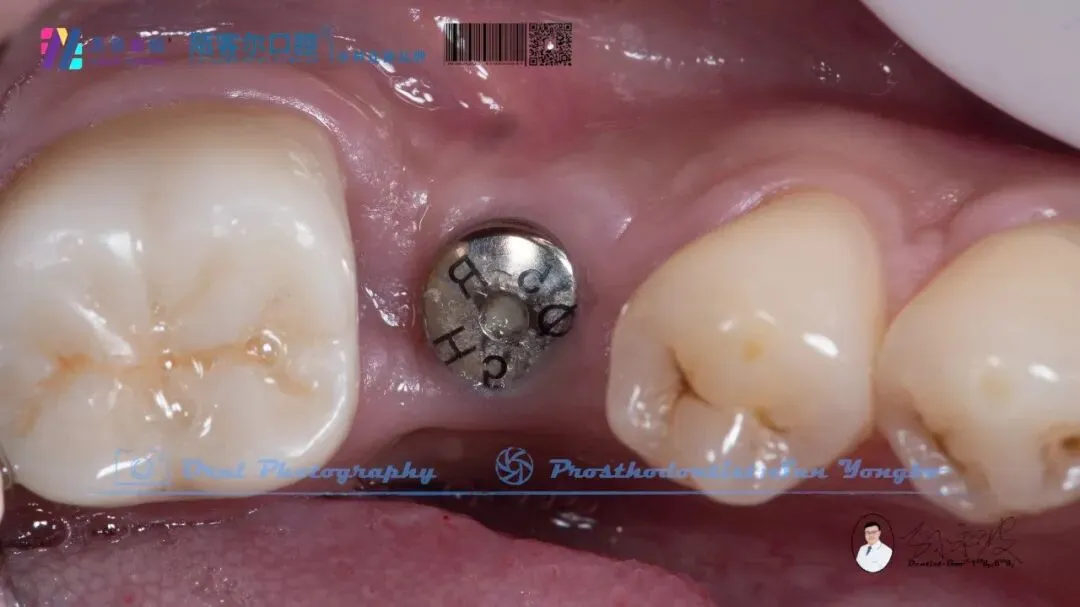

>【深圳牙医-孙永波】病例16丨右下后牙单颗缺失种植修复

【深圳牙医-孙永波】病例16丨右下后牙单颗缺失种植修复